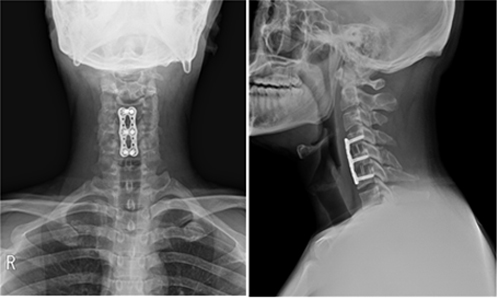

수술적 방법으로는 가장 일반적인 방법으로는 목의 앞쪽에서 디스크을 완전히 제거하고 골이식을 하는 방법이 가장 보편적으로 많이 사용되는 방법이며, 수술의 안정성이나 임상 결과 측면에서 수 십년 간의 오랜 임상 경험을 통하여 효과가 입증되어 있는 방법입니다.

두 번째로는 경추 인공디스크 삽입술을 들수 있습니다. 인공 디스크란 기존의 손상된 디스크를 제거하고 이를 인공물로 대치하는 방법입니다. 수술 방법은 일반적인 전방 고정술과 비슷하나 수술 후에도 그 부위의 운동을 유지시킬 수 있어 유합술로 인해 초래될 수 있는 인접마디 변성을 막을 수 있다는 큰 장점이 있습니다.

하지만 비용이 상대적으로 비싸고, 뼈의 퇴행성 변화가 심한 경우에는 사용할 수 없다는 단점이 있으며, 전세계적으로 임상 경험이 상대적으로 짧아 장기적인 임상 결과는 아직 연구 중입니다.